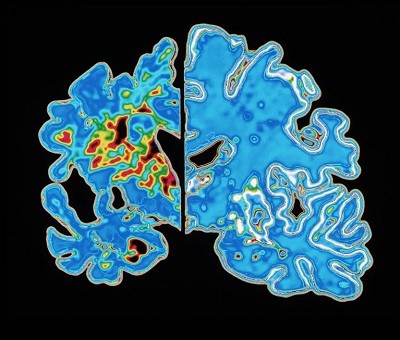

Adults whose brains still have strong neuron production seem to have better memory and cognitive function than do those in whom the ability wanes, finds a study published today in Nature1. The authors examined brain samples from deceased donors ranging from young adults to ‘super agers’ — people older than 80 with exceptional memory.

They found that young and old adults with healthy cognition generated neurons, a process called neurogenesis, at high levels for their age. The team estimated that the new neurons made up only a small fraction — 0.01% — of those in the hippocampus, a brain region that’s essential for memory. By contrast, in people experiencing cognitive decline, including individuals with Alzheimer’s disease, neurogenesis seems to falter: the researchers spotted fewer developing, or immature, neurons in those brain samples.

Surprisingly, a group of ‘super agers’ had an even higher number of immature neurons than did other groups, and significantly more than did those with Alzheimer’s. However, the group sizes were small, so the findings were not all statistically significant.